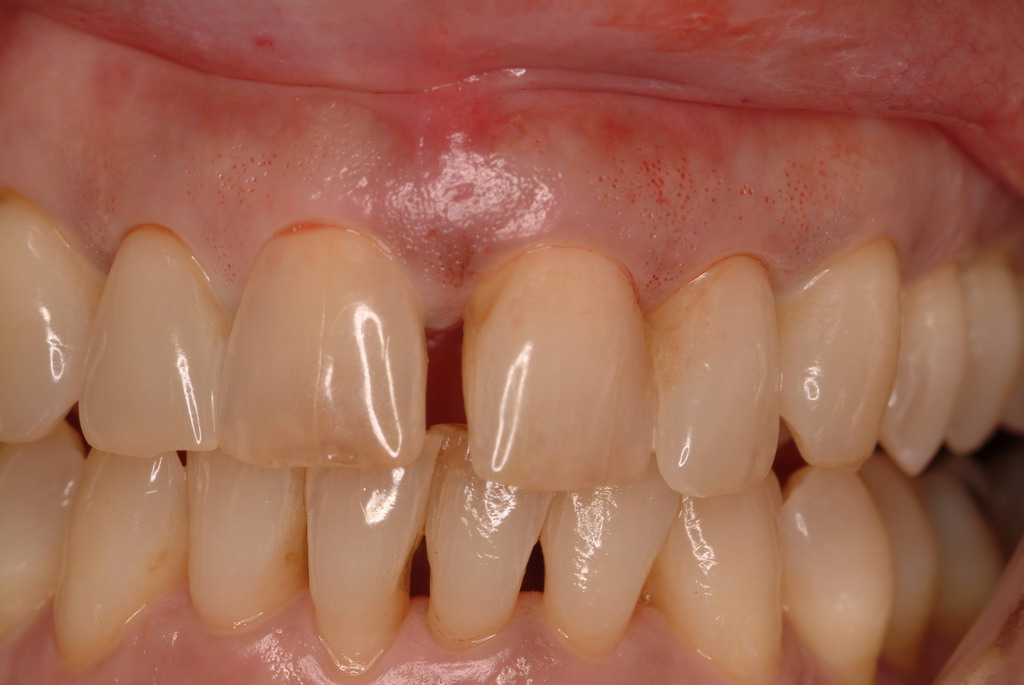

In a case with an intrabony defect, such as with the patient in Figure 17, a periodontist might suggest sacrificing supporting bone to remove the osseous defect. Doing this might lead to issues related to tooth mobility, esthetics, caries, and hypersensitivity.

The patient had been referred for an implant consultation for the mandibular right canine. She had very deep probing depths on the lingual. When the flap was raised, a significant amount of subgingival calculus was seen as a local risk factor (Figure 18). However, she had no significant pathology to remove from the situation. Debridement was performed the same as in Case 3 with the rotary ultrasonic and manual instrumentation.

A significant intrabony defect around tooth No. 27.

Figure 17

Subgingival calculus and severe bone loss.

Figure 18